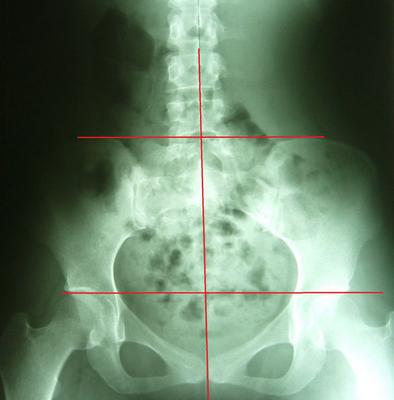

一般最常见到骨盆歪斜的案例包括产后骨盆不正、车祸、撞击、跌倒、姿势不良…等等造成。骨盆歪斜的典型症状包括腰部、髋臀部、腿、膝部疼痛。列举三个自在美国取得脊医执照以来曾经处理过骨盆歪斜相当明显的案例。都是骨盆部位曾经遭受撞击。案例A是超过十年以上的陈年车祸旧伤、另一案例B是急性摔伤(两天内)的案例。两者的X光片都依照美国脊医X摄影方式采站姿摄影评价。借此同时评价骨盆在重力(gravity)影响下的反应。也可以泯除躺歪斜摄影而造成图像不正的情况。最简单的评价要点包括骨盆高低边?中线是否穿越耻骨联合?左右两边是否对称?我简单的几条线一画,相信连外行人也可以看出明显的骨盆歪斜的情况。案例A属陈旧性伤害在调理约两个月后明显降低腰臀腿部的不舒服。而案例B属急性伤害,案例B在调理近三周后骨盆疼痛由原先的持续疼痛降低为完全不痛。之后的骨盆X光摄影重新评价也显示骨盆旋转的问题大幅改善。

案例B:左图调理前骨盆严重歪斜左右极不对称 ;右图调理后骨盆歪斜改善骨盆圈呈现对称心型圆弧